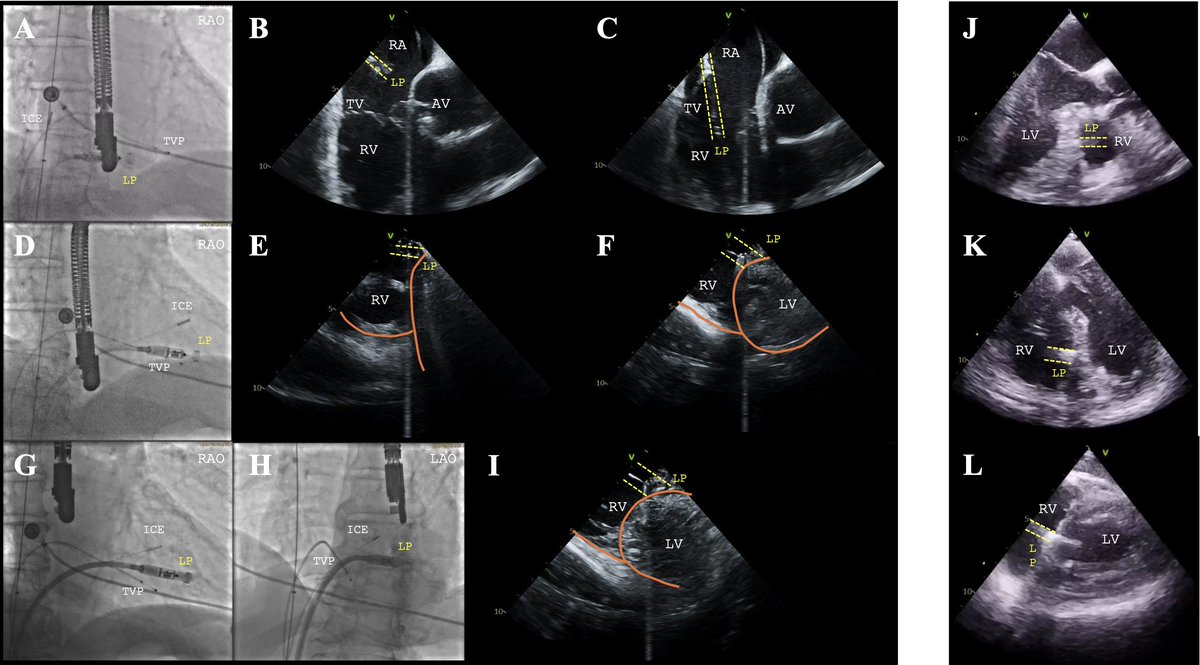

**Study 3: Step-by-step approach to ultrasound-guided leadless pacemaker implantation @DJ_Lakkireddy @MohitTuragam @jkewcharoen et al share a practical, image-guided protocol using TTE, ICE, or TEE to optimize LP placement and reduce contrast/radiation exposure. *Echo confirms